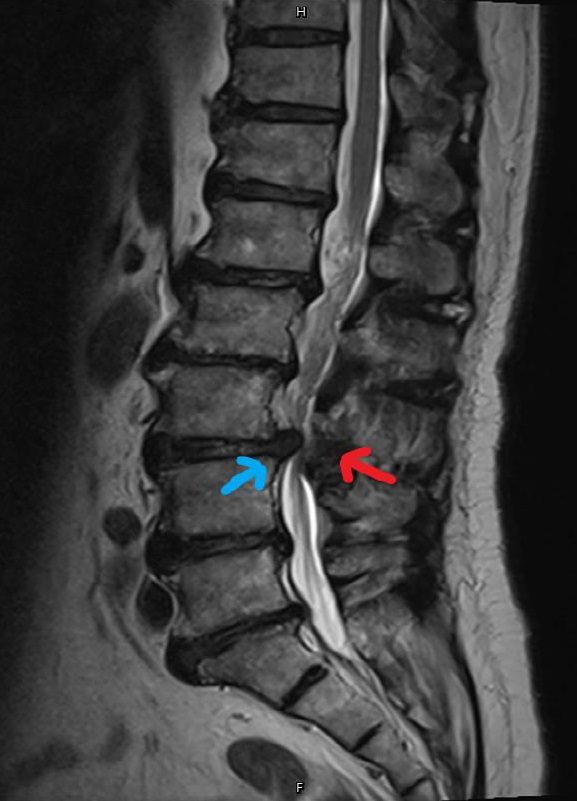

圖三 核磁共振顯示椎間盤突出嚴重壓迫神經(如藍色箭頭);關節韌帶增生(如紅色箭頭),造成腰椎管腔狹窄。